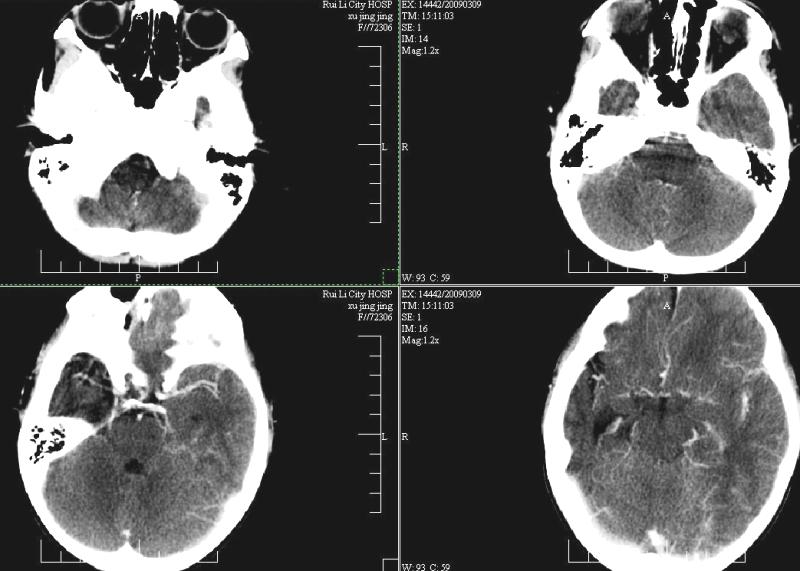

标题: PED1810:F,9岁。头痛,昏倒,一周一次,共半年。 [打印本页]

标题: PED1810:F,9岁。头痛,昏倒,一周一次,共半年。

ct:右顶叶脑软化灶合并右侧大脑半球发育不良可能。

右侧大脑半球脑萎缩。

支持楼主!右侧强化明显较左侧低.可能血管引起的吧.

支持楼主!右侧强化明显较左侧低.可能由血管发育不良引起的吧.

支持大脑发育不全----右侧大脑中动脉较对侧细小。建议cta 或mra 检查